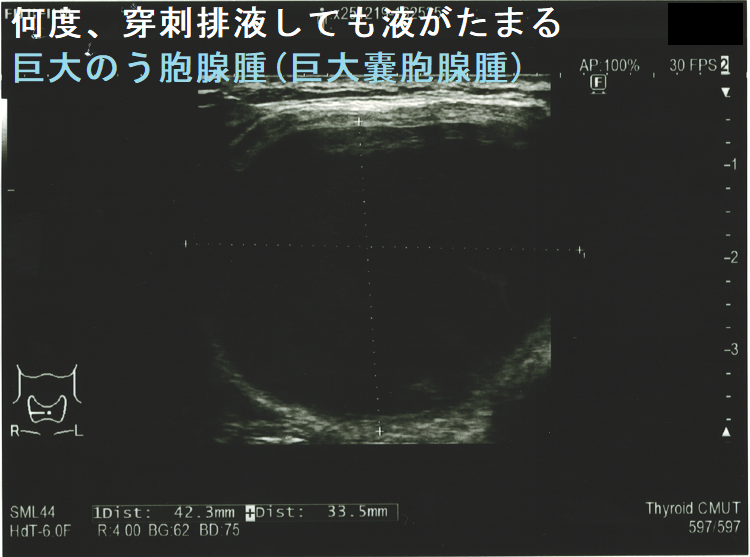

手術すべきか迷う巨大甲状腺のう胞腺腫(巨大甲状腺嚢胞腺腫)。横径 5.49cmで、ほぼ6cm。80歳以上なら全身麻酔のリスクを冒してまで手術しなくて良いかもしれません。せいぜい次項の経皮的エタノール注入療法(PEIT)ぐらいでしょう。

頻回に穿刺排液しても液がたまる巨大のう胞腺腫(巨大嚢胞腺腫)は、良性腫瘍(のう胞型濾胞腺腫:嚢胞型濾胞腺腫)であっても手術適応になります。単に、のう胞(嚢胞)と呼ばれる事も多いですが、甲状腺組織の破壊・変性によるのう胞変性(嚢胞変性)でなく、れっきとした腫瘍です。

(岩手県立中央病院の報告) 97 x 71 x 60 mmの巨大な甲状腺のう胞腺腫(甲状腺嚢胞腺腫)で、排液後1週間以内に液が再貯留し始めたため、甲状腺半葉切除したそうです。病理標本を確認すると、のう胞周囲は炎症が強く、炎症性浸出液の可能性が考えられました。(第57回 日本甲状腺学会 P2-070 巨大な甲状腺嚢胞により経口摂取困難となった一例)